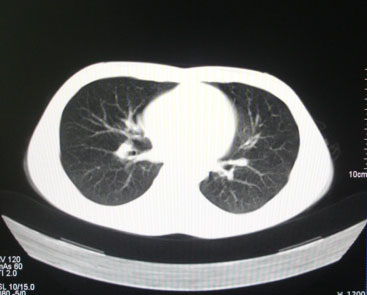

标题: CT26938:单发肺窗

病人17岁。咳嗽伴血丝痰2年?外院x片示左上肺椭圆形影,疑胸腺瘤

左肺尖见占位,建议上传纵隔窗及向上扫描。

左上纵隔占位性病变?